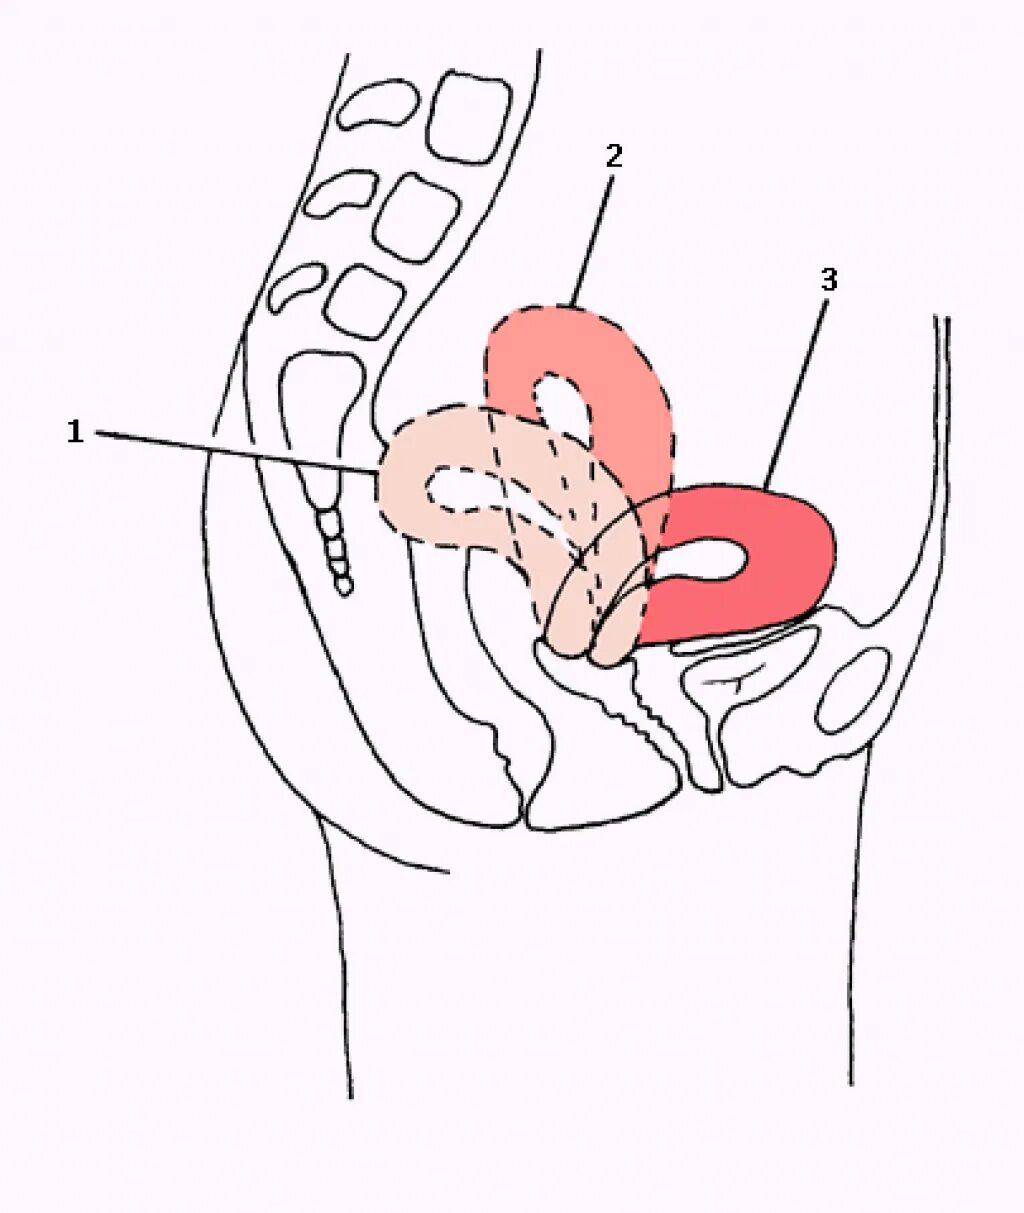

Можно ли забеременеть при загибе матки